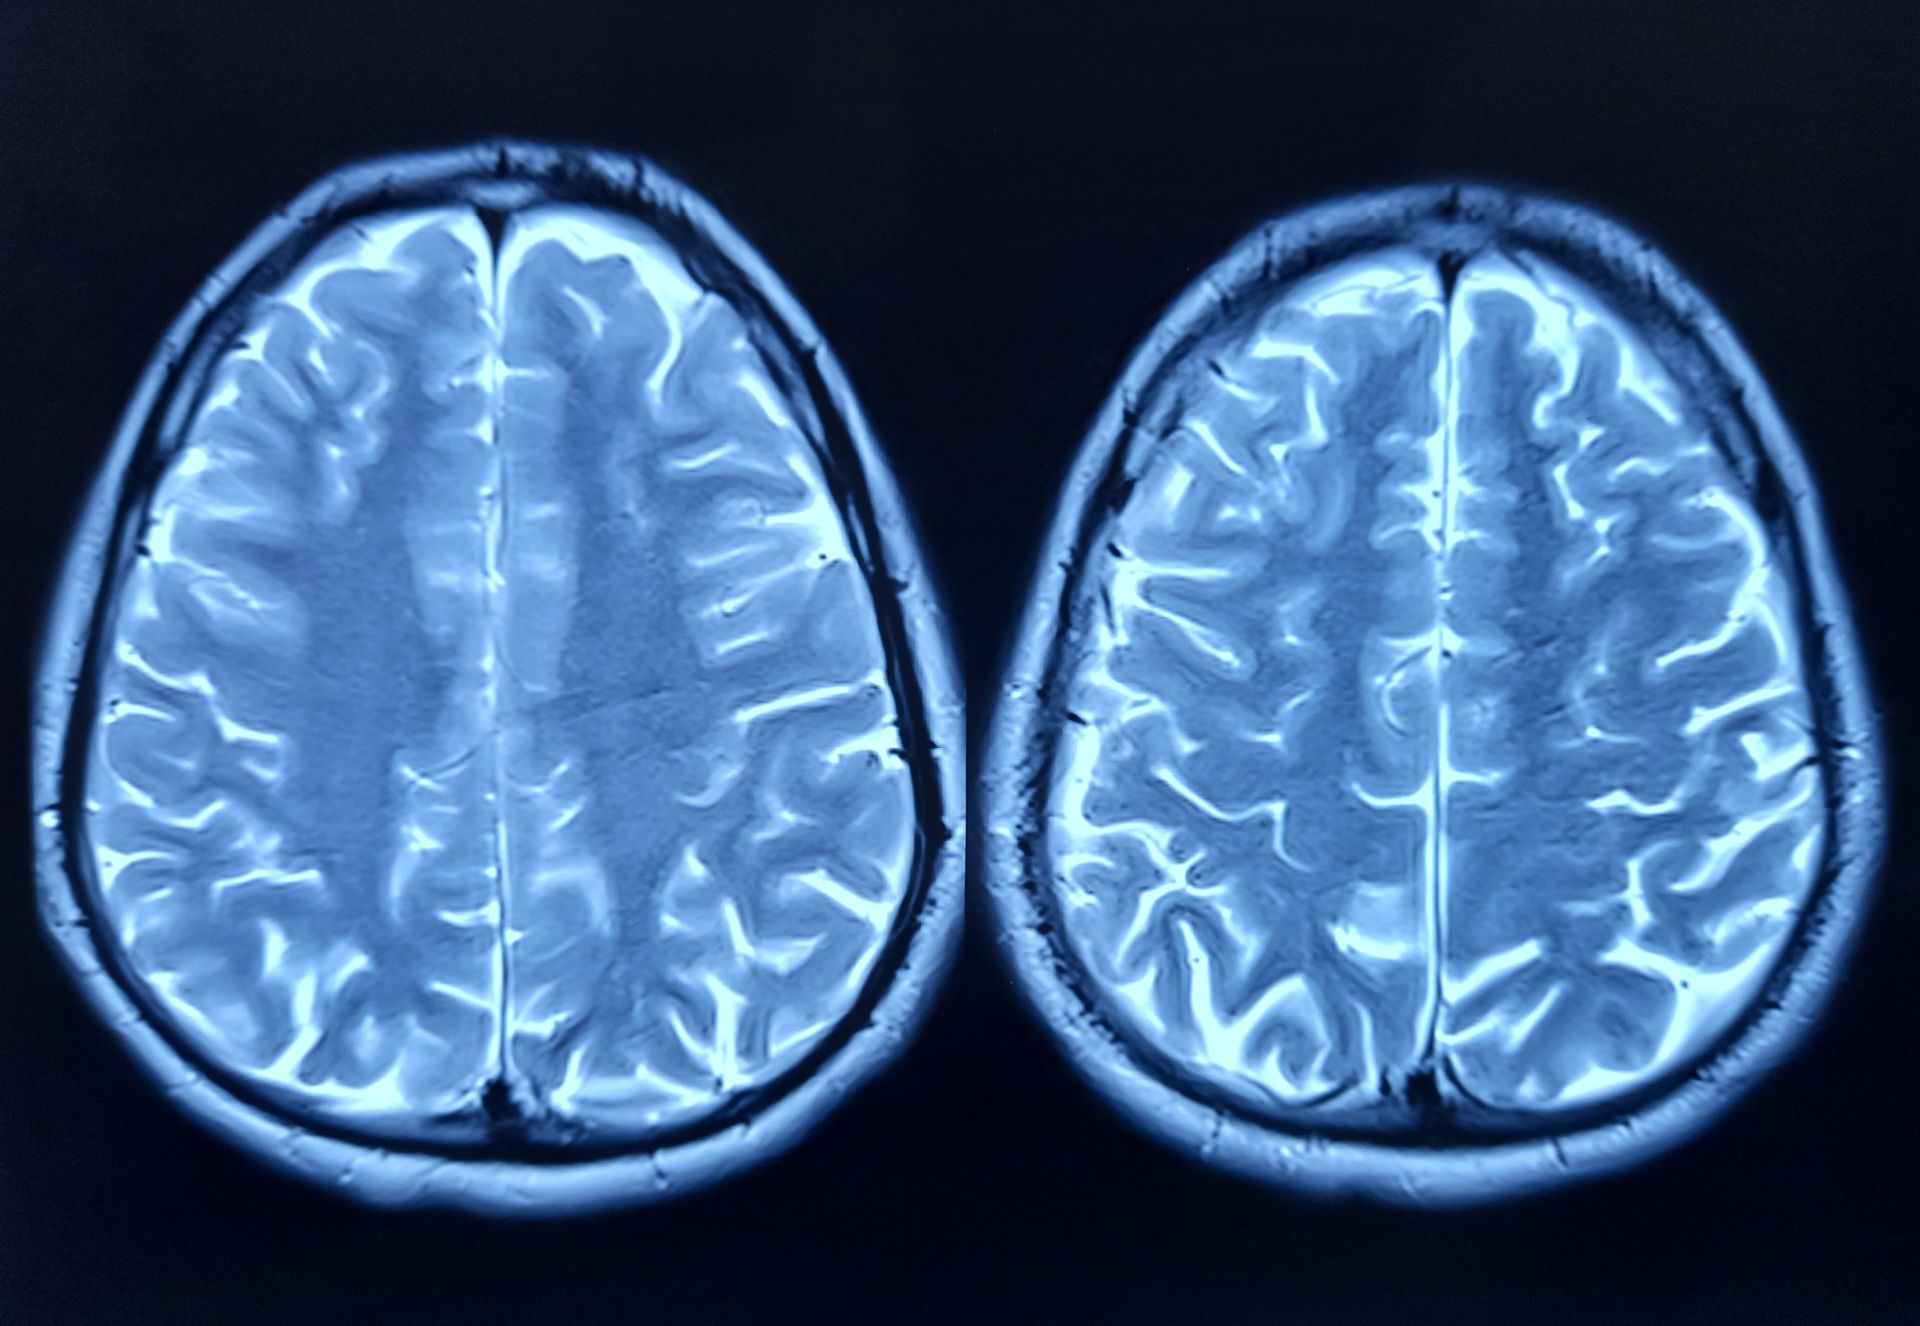

Un nou indiciu în misterul îmbătrânirii creierului a fost descoperit de cercetători. Conform studiilor recente, o proteină numită FTL1 joacă un rol semnificativ în deteriorarea conexiunilor neuronale din hipocamp, partea creierului implicată în învățare și memorie. La șoarecii bătrâni, nivelurile ridicate ale acestei proteine au fost constatate ca fiind cauza principală a declinului cognitiv. Cercetătorii de la UCSF au urmărit evoluția genelor și proteinelor din hipocampul șoarecilor de-a lungul timpului, comparând speciile tinere cu cele în vârstă. Rezultatele au indicat faptul că proteina FTL1 este mereu mai prezentă la animalele mai bătrâne, ceea ce coincide cu o diminuare a conexiunilor neuronale și o performanță scăzută în teste de memorie. Acest lucru indică faptul că FTL1 poate fi un factor cheie în mecanismele de îmbătrânire a creierului.

Pentru a verifica impactul proteinei asupra funcției cerebrale, cercetătorii au crescut artificial nivelul FTL1 la șoarecii tineri, rezultând o deteriorare a funcțiilor cerebrale, asemănătoare cu cele observate la cei bătrâni. În schimb, reducerea nivelului FTL1 la șoarecii bătrâni a a dus la îmbunătățirea conexiunilor neuronale și a performanței cognitive. Aceste rezultate sugerează că manipularea nivelului acestei proteine poate avea efecte benefice asupra sănătății creierului. Saul Villeda, director adjunct al UCSF și autor principal al studiului, afirmă că această intervenție nu doar ameliorează simptomele îmbătrânirii cerebrale, ci poate inversa unele dintre efectele negative. „Este cu adevărat o inversare a deficiențelor”, a declarat el, subliniind importanța acestei descoperiri în înțelegerea procesului de îmbătrânire a creierului.

Studiile ulterioare au evidențiat faptul că FTL1 afectează și modul în care celulele cerebrale utilizează energia. La șoarecii în vârstă, nivelurile crescute ale proteinei au încetinit metabolismul celular în hipocamp, ceea ce poate contribui la deteriorare. Totuși, experimentele cu compuși care stimulează metabolismul celular au demonstrat că aceste efecte negative pot fi contracarate, deschizând posibilitatea dezvoltării unor tratamente specifice. Villeda consideră că aceste constatări reprezintă un pas înainte spre terapii care vizează direct proteina FTL1, cu scopul de a contracara declinul cognitiv asociat bătrâneții. „Vedem tot mai multe oportunități de a atenua cele mai grave consecințe ale bătrâneții”, a afirmat el, evidențiind potențialul de a dezvolta intervenții mai eficiente pentru sănătatea creierului și longevity. Un fapt concret în acest context este că, în 2024, cercetările clinice pe subiecți umani pentru terapii ce vizează reducerea nivelurilor de FTL1 sunt în faza de planificare, cu speranța că rezultatele vor fi publicate în următorii doi ani. Sursa: DescoperaO proteină influențează procesul de îmbătrânire a creierului și memoria